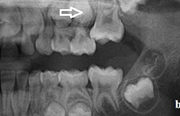

Esimeste molaaride (purihammaste) lõikumine

Esimeste molaaride (purihammaste) lõikumine. 1. molaaride ektoopilise lõikumise jälgimine. Ülemised ja alumised esimesed purihambad e. molaarid lõikuvad orienteeruvalt6-7-aastaselt piimahammaste rea lõppu. Enamasti lõikuvad samanimelised jäävhambad paaridena. Normaalne lõikumise Loe edasi »

- valehambumus (18)